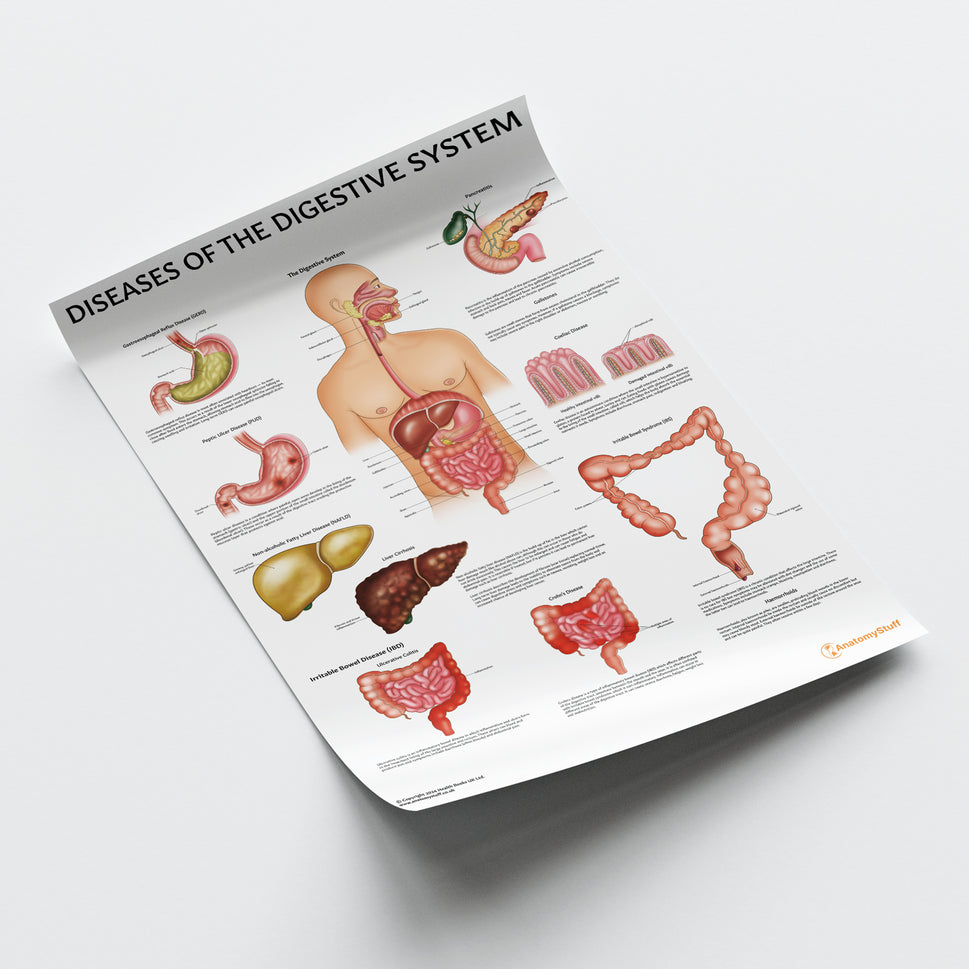

Enhance medical education with our collection of digestive system anatomical models including the stomach, liver, gallbladder, pancreas & colon models. Discover the anatomy of healthy organs as well as common gastrointestinal diseases such as stomach ulcers, gallstones and liver cirrhosis. Our digestive system anatomy posters are ideal for study and patient education.

At AnatomyStuff we stock a diverse range of digestive system anatomical models to suit your training needs. From budget models and affordable medical education posters to highly advanced 3D printed bowel models, you can transform medical training and patient education. As well as our own exclusive collection, we are proud resellers of 3B Scientific, Anatomy Lab, Denoyer-Geppert Science Company, ESP Models, Erler Zimmer and GPI Anatomicals. Explore our exclusive collection of digestive system anatomy charts, posters, fine art prints and digital anatomy study guides. Discover the anatomy of key organs like the liver, stomach, pancreas and bowel as well as the pathophysiology of common conditions like peptic ulcer disease, coeliac disease, IBD and much more. We have anatomy posters suitable for school children all the way up to medical degree level. From a liver anatomy poster to a digital study guide all about common GI disorders, find exactly what you need right here to enhance medical training and patient education.